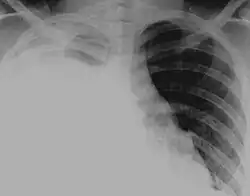

Anteroposterior chest X-ray of a pleural effusion. The A arrow shows fluid layering in the right pleural cavity. The B arrow shows the normal width of the lung in the cavity.